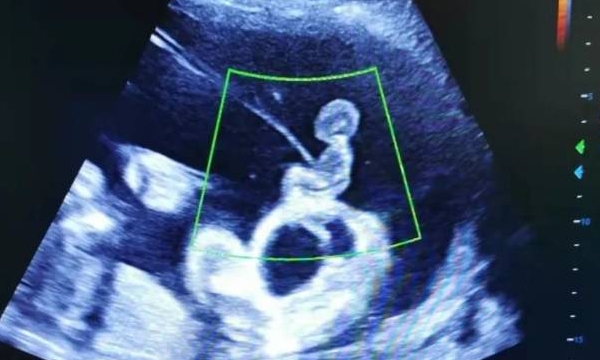

16周的“结构初现”:此时胎儿长约16厘米,头部、四肢等基本结构已清晰可见。超声可测量双顶径、股骨长等数据,还能观察鼻骨发育(唐氏儿常出现鼻骨缺失)。但胎儿较小,部分器官如心脏的细节可能显示不全。

18周的“细节升级”:胎儿增至约20厘米,器官发育更完善。超声不仅能清晰看到心脏四腔结构,还能通过“软指标”(如肠管强回声、肾盂轻度扩张)辅助判断染色体异常风险。某三甲医院数据显示,18周超声联合唐筛的检出率比单独检测提高15%。